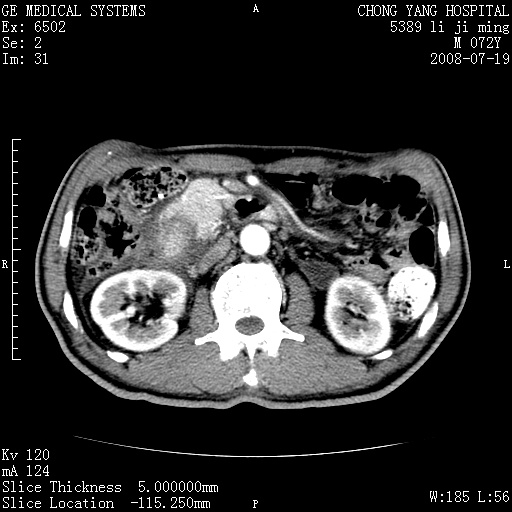

以下是引用zjzjr在2008-7-19 20:57:00的发言:[br]胰头增大,边缘模糊,周围可见渗出影,右侧肾前筋膜增厚.支持胰腺炎.

以下是引用yangyudong333在2008-7-20 6:56:00的发言:[br]胰腺增大尤以胰头明显,边缘模糊,周围可见渗出影,右侧肾前筋膜增厚,肠管於涨.支持胰腺炎

以下是引用不学无术在2008-7-19 23:15:00的发言:[br]胰腺增大尤以胰头明显,边缘模糊,周围可见渗出影,右侧肾前筋膜增厚,肠管於涨.支持胰腺炎